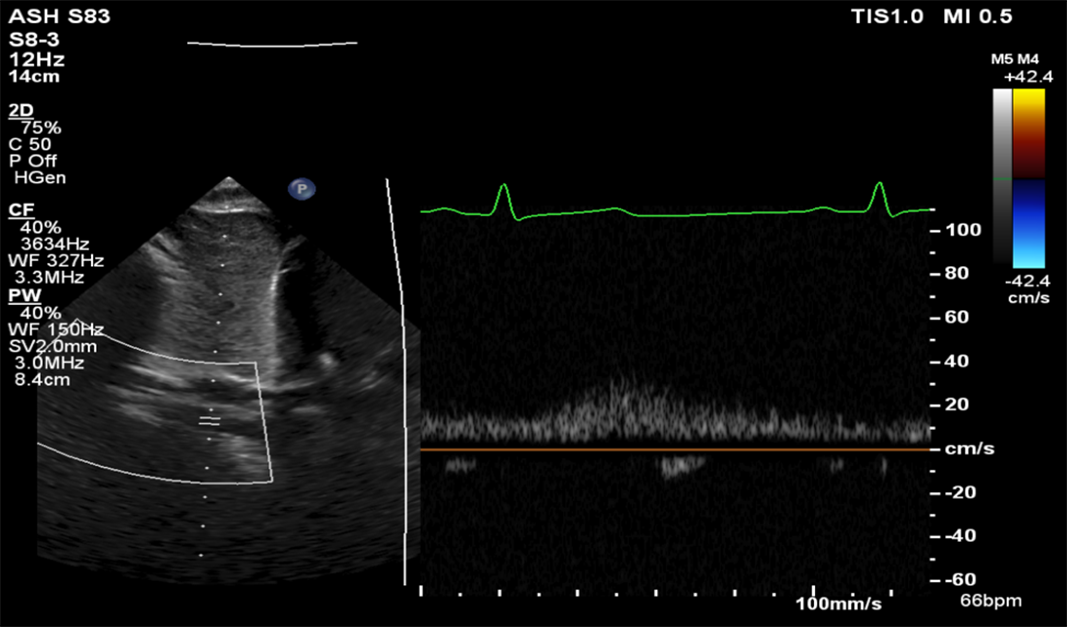

Aortic arch contour was abnormal and appeared to taper at the isthmus. Doppler velocity at the isthmus was within normal limits (1.1 m/s), but a pathologic flow profile with continuation through diastole was noted (Fig 1). Lack of pulsatility and low-velocity continuous flow was found on abdominal descending aorta interrogation (Fig 2). Exam revealed the absence of distal pulses and upper extremity hypertension (139/87 mmHg) with a significant gradient to the lower extremity (72/48 mmHg). CT angiogram confirmed the suspected diagnosis of coarctation of the aorta (Fig 3) and showed extensive vertebral collateralisation supplying the descending aorta. He underwent successful surgical coarctectomy with a lumenal diameter of the excised aortic isthmus found to be less than 1 mm diameter (Fig 4).

Figure 3. CT angiogram showing severe short segment juxtaductal coarctation of the aorta with the luminal diameter measuring 1 × 1 mm with well-formed collateral circulation supplying the descending thoracic aorta through the paravertebral arteries.